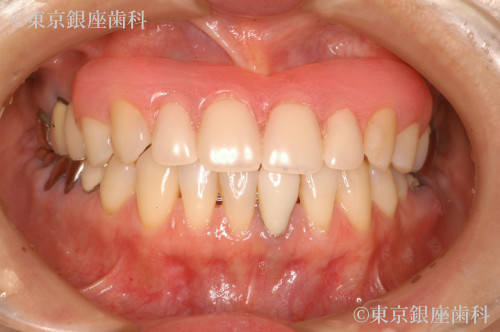

Before

After

前歯4本を入歯からインプラントに変更